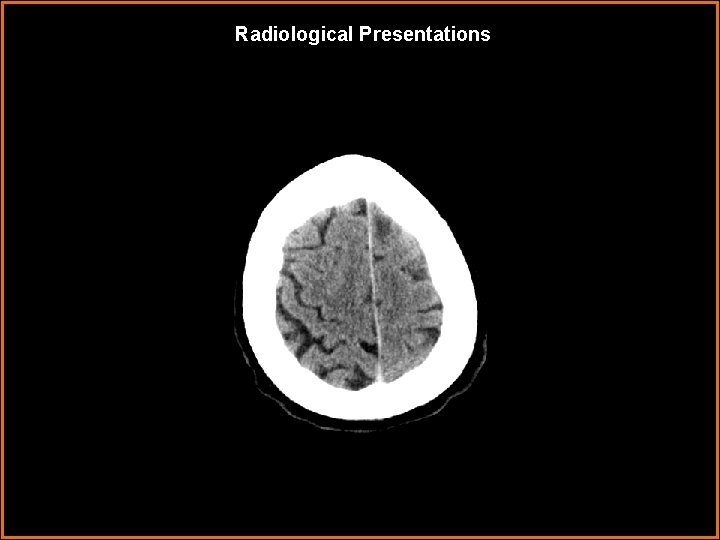

Findings and Differentials Findings: CT: Multiple mass-like areas of low attenuations in the supratentorium within the left anterior frontal lobe, left posterior frontal lobe, and right insular/ periventricular white matter. No hemorrhage or calcifications. Differentials: • Metastases • Multiple cerebral abscesses • Multifocal glioblastoma multiforme • Toxoplasmosis • Tumefactive demyelinating lesions • Progressive multifocal leukoencephalopathy